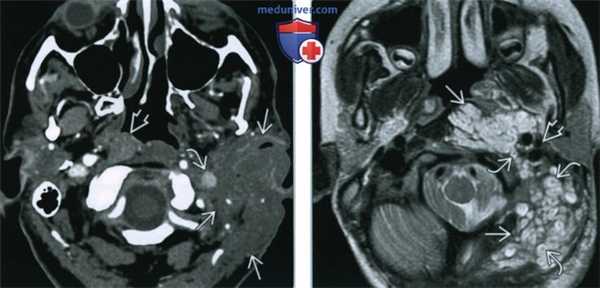

(Слева) КТ с КУ. Мягкотканное образование с инфильтрирующим ростом, которое расположено в подкожных и глубоких тканях и минимально накапливает контраст. Опухоль окружает левую внутреннюю яремную вену. Обратите внимание на небольшое образование в предпозвоночных мышцах, умеренно накапливающее контраст.

(Справа) МРТ Т2ВИ, аксиальная проекция. Характерные МР-признаки плексиформной нейрофибромы в предпозвоночных и околопозвоночных тканях, окружающей сонное влагалище. Сигнал от многодольчатого образования гиперинтенсивный, за исключением центрального участка.

3. КТ при плексиформной нейрофиброме головы и шеи:

• КТ с КУ:

о Солидное образование с инфильтративным ростом, умеренно накапливающее контраст

4. МРТ при плексиформной нейрофиброме головы и шеи:

• Т1ВИ:

о Изоинтенсивный мышце сигнал

• Т2ВИ FS:

о Гиперинтенсивное дольчатое образование, захватывающее несколько смежных пространств

о Характерны центральные участки низкого сигнала: «признак мишени»

• Т1ВИ FS с КУ:

о Незначительное или умеренное накопление контраста